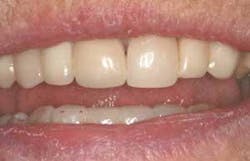

Figure 19 - Full-smile view of completed case. The patient is extremely pleased with the final functional and esthetic result.

Although only three-week postop results have been documented, already the technique holds promise. Papilla formation has occurred and the implant-crown unit is stable and healthy so far. The patient is taking more personal pride in her restoration and in her appearance, as evidenced by a dramatic improvement in plaque removal and overall oral hygiene observed at her three-week checkup.